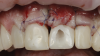

The patient in this case had undergone implant therapy at the site of tooth No. 9 and was restored with a cement-retained restoration more than 5 years prior. At presentation, the site demonstrated a peri-implant soft-tissue dehiscence that extended approximately 3-mm apical to the gingival margin of tooth No. 8. Thin and erythematous marginal tissue was evident at the zenith (Figure 2). The crown was removed, and a partial thickness flap was reflected using a papilla-sparing incision design. This revealed that the implant was positioned too far facially and that its body was visible through a very thin layer of bone (Figure 3 and Figure 4). The first objective of treatment was to minimize the facial extent of the emerging abutment and crown. To accomplish this, the facially positioned abutment and implant crown margin were both recontoured. The second treatment objective was to provide additional supracrestal soft tissue that would more adequately maintain the peri-implant margin. The tuberosity was selected as a donor site due to its dense, high-quality connective tissue, low propensity for shrinkage, and association with minimal patient discomfort. Once the graft was secured (Figure 5 through Figure 7), the flap was coronally positioned (Figure 8). After a healing period of 2 weeks, the margin of tooth No. 9 exhibited an ideal position in relation to its contralateral counterpart and demonstrated increased soft tissue thickness (Figure 9). Three months postoperatively, further healing had improved the esthetics and the position of the margin had been maintained (Figure 10).

(3.) The crown was removed, and a partial thickness flap was reflected using a papilla-sparing incision design, which revealed that the implant was positioned too far facially and that its body was visible through a very thin layer of bone.

Figure 3

(4.) The crown was removed, and a partial thickness flap was reflected using a papilla-sparing incision design, which revealed that the implant was positioned too far facially and that its body was visible through a very thin layer of bone.

Figure 4